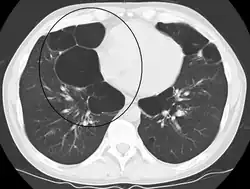

Bullous

When the subpleural bullae are significant, the emphysema is called bullous emphysema. Bullae can become extensive and combine to form giant bullae. These can be large enough to take up a third of a hemithorax, compress the lung parenchyma, and cause displacement. The emphysema is now termed giant bullous emphysema, more commonly called vanishing lung syndrome due to the compressed parenchyma.[28] A bleb or bulla may sometimes rupture and cause a pneumothorax.[17]

Lung transplantation – the replacement of either a single lung or both (bilateral) – may be considered in end-stage disease. A bilateral transplant is the preferred choice as complications can arise in a remaining single native lung; complications can include hyperinflation, pneumonia, and the development of lung cancer.[60] Careful selection as recommended by the National Emphysema Treatment Trial (NETT) for transplant surgeries is needed as in some cases there will be an increased risk of mortality.[49] Several factors, including age and exercise tolerance using the BODE index need to be taken into account.[60] A transplant is considered only when there are no serious comorbidites.[50] A CT scan or a ventilation/perfusion scan may be useful to evaluate cases for surgical interventions and to evaluate post-surgery responses.[61] A bullectomy may be carried out when a giant bulla occupies more than a third of a hemithorax.[50]